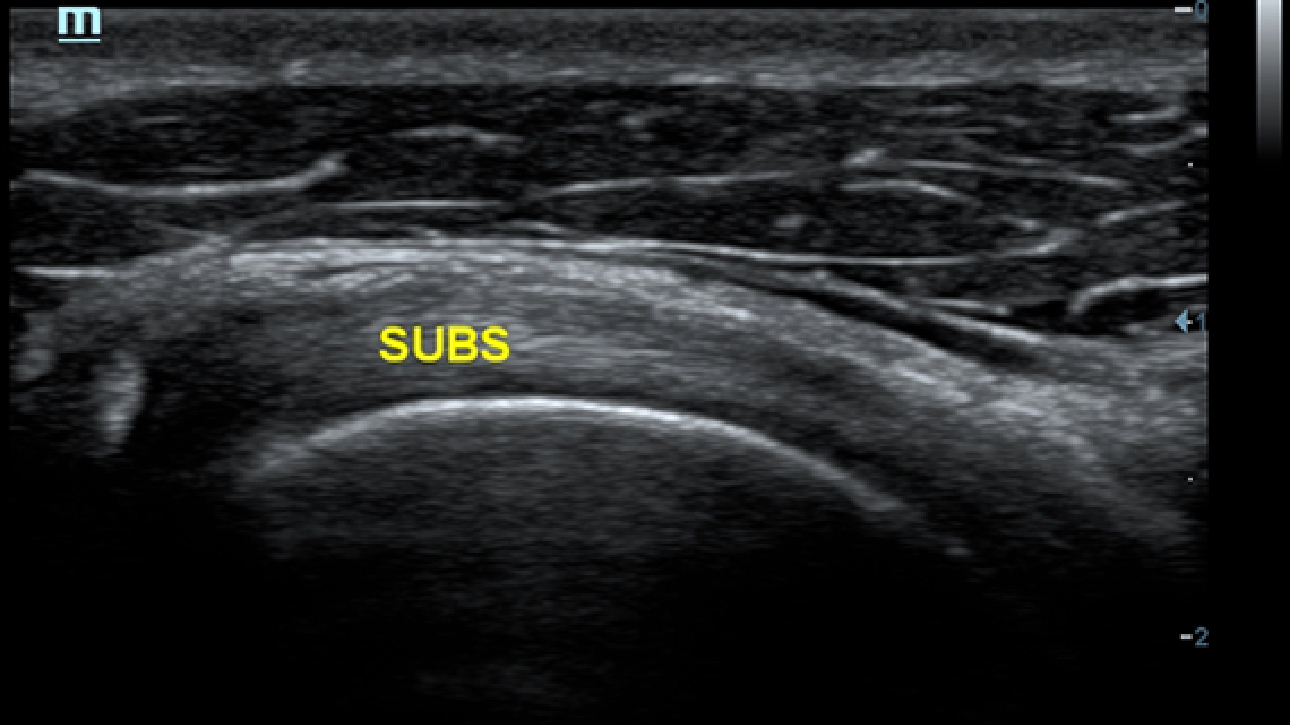

X-Insight is een inzichtelijke oplossing om meer visie te krijgen.

De gloednieuwe oplossing van Mindray is het geslaagde product dat is voortgekomen uit voortdurende klantinzichten in klinische behoeften in combinatie met steeds evoluerende, geavanceerde ultrasoundtechnologie?n. Vol energie en gebrand op toekomstgerichte inzichten en eindeloze mogelijkheden: dankzij de verhoogde schaalbaarheid wordt de oplossing continu verbeterd.

Als allround partner zet DC-60 Exp met X-Insight zich in om een allesomvattende oplossing te zoeken waarmee u alle aspecten van uw dagelijkse klinische activiteiten gemakkelijk en trefzeker kunt beheren.

De DC-60 Exp met X-Insight is ontworpen op basis van diepgaand inzicht in klantbehoeften om hoge effici?ntie met nauwkeurige beeldverwerking te leveren, dankzij eXacte helderheid, eXceptionele intelligentie en eXcellente ervaring.